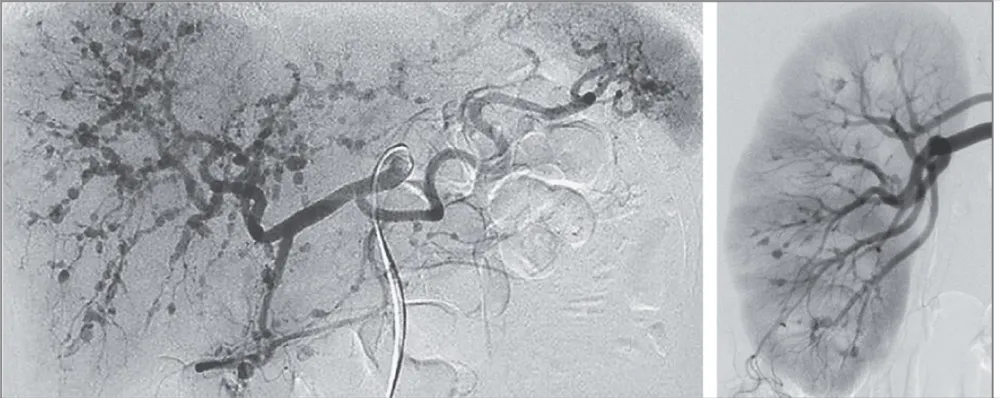

Necrose cortical renal, uma causa subdiagnosticada de IRA

Necrose cortical renal, uma causa subdiagnosticada de IRA

Frequentemente nos deparamos com pacientes que evoluem com quadro de IRA "desproporcional" ao quadro séptico, necrose cortical renal é uma entidade que não pode ser esquecida, principalmente em pacientes com complicações obstétricas